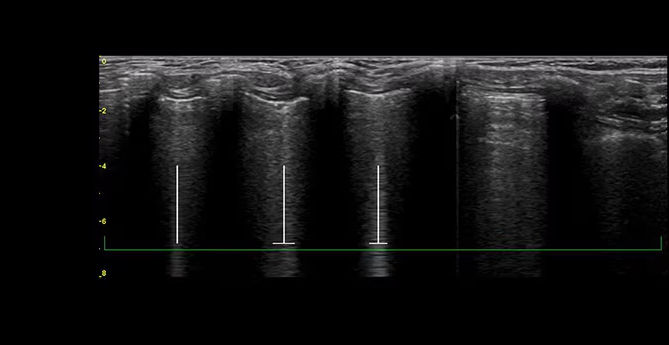

Highlight and count B-lines, in real time

With the Auto B-Lines* tool, you can calculate overall lung score in one step. Use it in conjunction with Lung Sweep to highlight B-lines and display the frame with the most B-lines per rib space.

peds-auto-b-lines-desktop